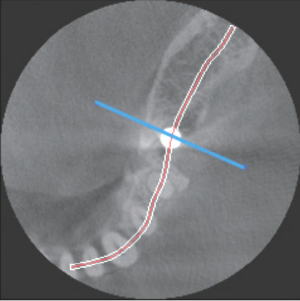

下顎奥歯に埋入したインプラントのCT画像

咬合平面に平行に根の真ん中付近を切断したところ。 |